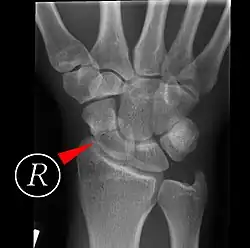

Röntgenbild einer Skaphoidfraktur rechts. Die Frakturlinie ist mit dem roten Pfeil markiert.

Die Verletzung des Kahnbeins macht drei Viertel aller Handwurzelbrüche aus. Sie entsteht in der Regel durch direkte Gewalteinwirkung, zum Beispiel durch einen Sturz auf die nach hinten überstreckte (dorsalextendierte) Hand mit einem Aufprall auf deren speichenseitige (radiale) Hälfte. Die genaue Höhe des Bruchs hängt dabei von der Stärke der Überstreckung und speichenseitige Seitbewegung (Radialabduktion) der Hand im Augenblick des Aufpralls ab.[1]